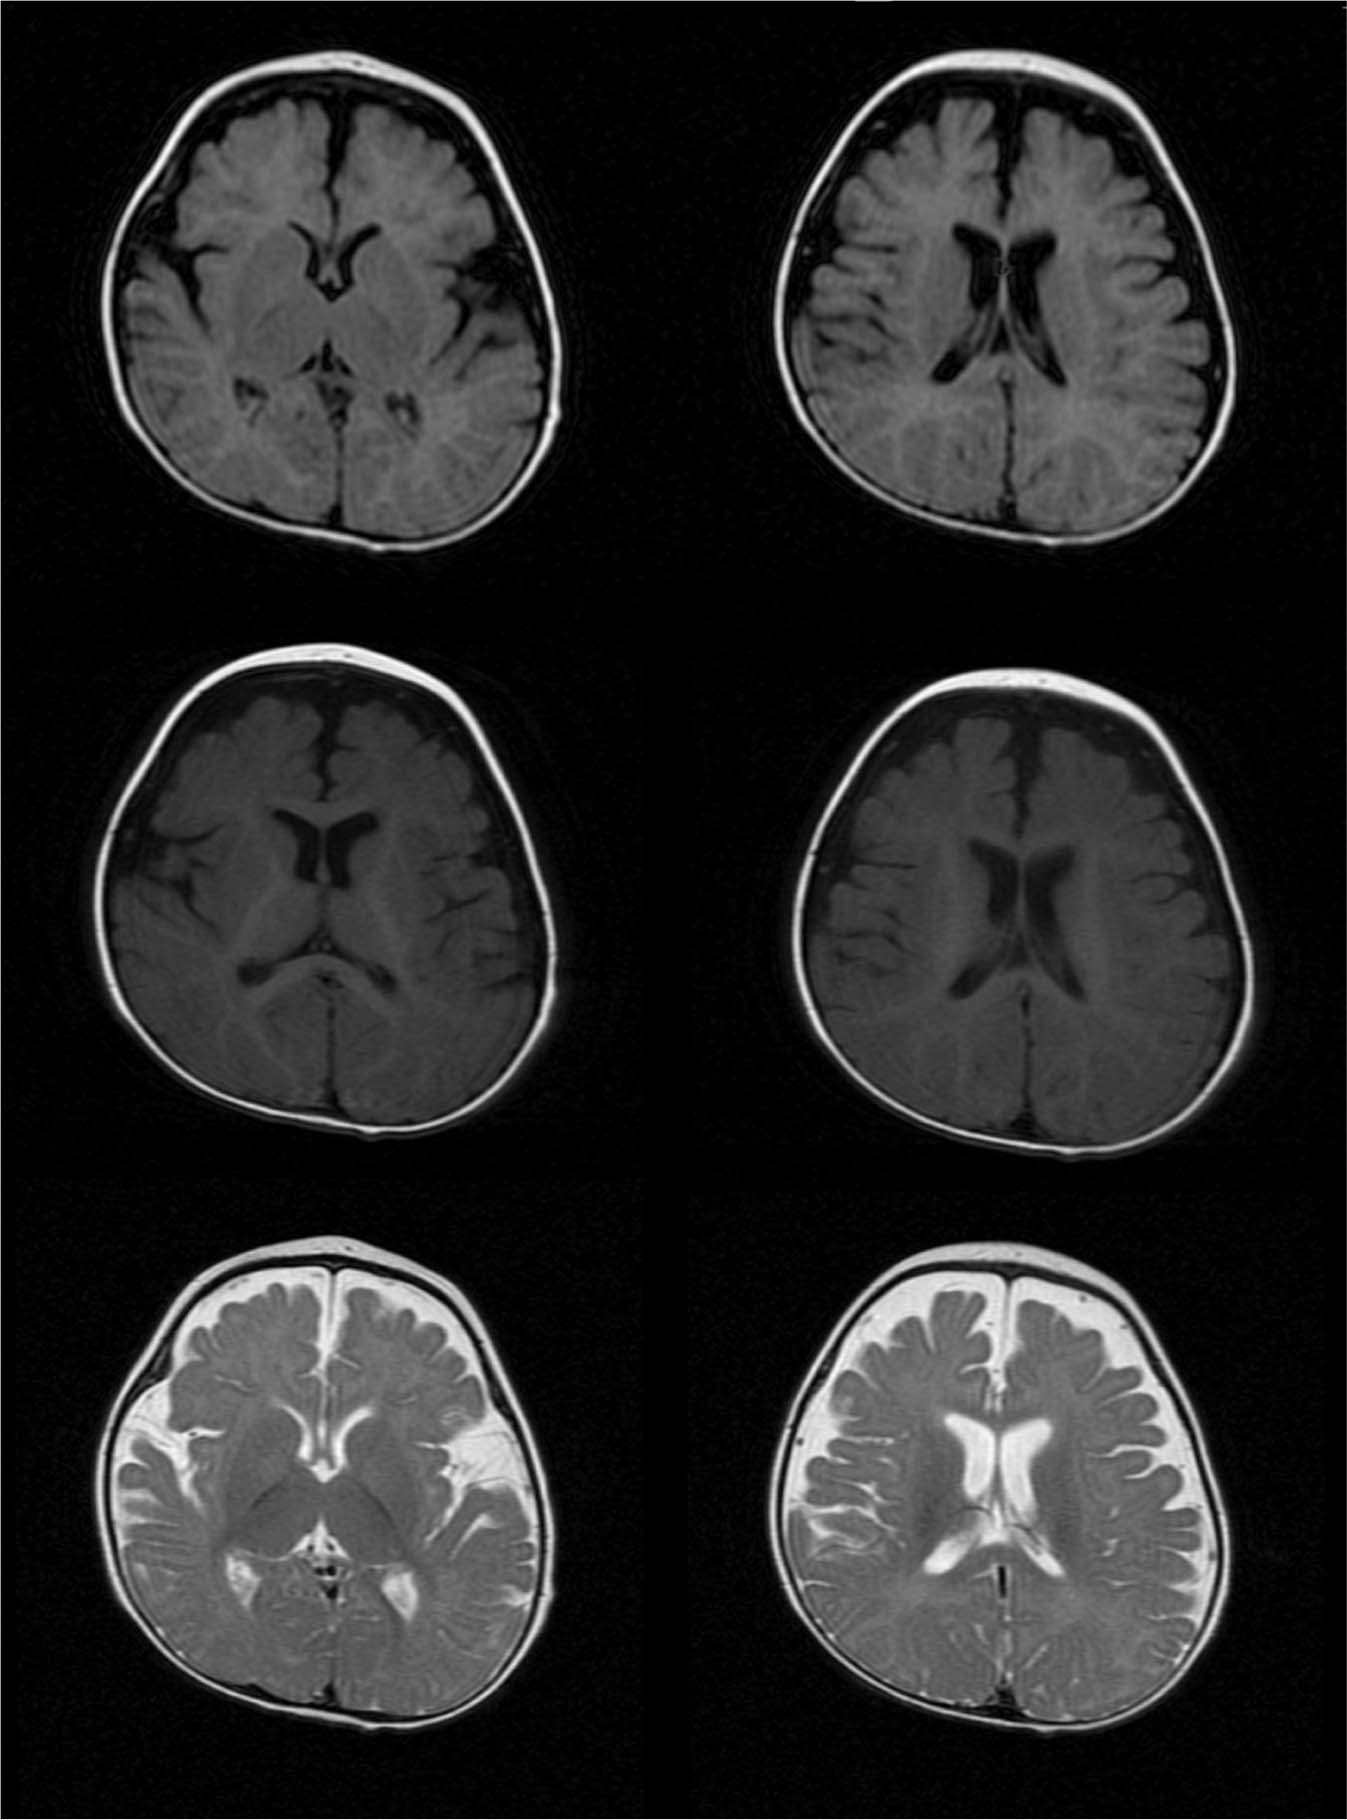

Fig. 2: Brain MRI of the proband. | Human Genome Variation